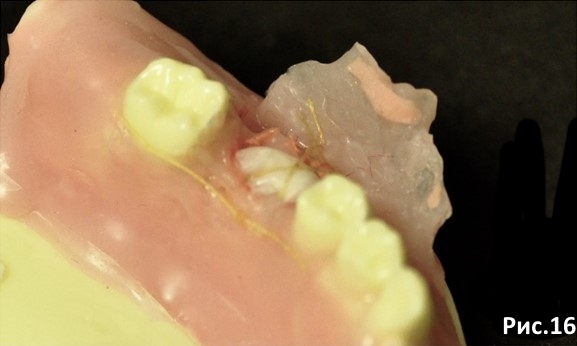

Обратите внимание: узел располагается с язычной стороны. Рис.16